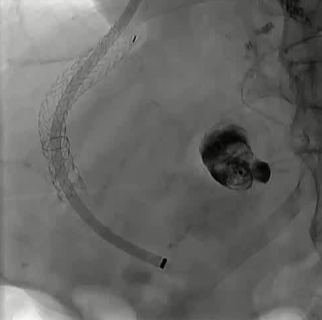

栓塞材料的可及性(例如病灶栓塞材料的可到达性)accessability (e.g. reachability of the nidus) 栓塞的预期深度intended deepness of embolization 如果需要让栓塞填满最后1mm 预期效果(例如:门静脉栓塞的炎症)intended effect (e.g. inflammation in PVE) 凝血状态(达到止血效果所需的时间)coagulation state (duration until hemostasis) 并发症(过敏、心律不齐、肺动脉高压、肝纤维化等)comorbidities (allergies, arrythmia, pulmonary hypertension, lung fibrosis etc.) 处于危险中的结构(包括下游部分-downstream和反流部分) structures at risk (downstream & backwash) 靶病变定位(浅层与深层) target lesion localization (superficial vs. deep) 不会选择一些会引起炎症的东西,因为那会病人来说真的很痛苦浅层病变 栓塞所需的速度(例如:危及生命的出血情况)required speed of embolization (e.g. life threatening hemorraghe) 院外专业人员(DSA技术人员和介入放射科医生)local expertise (technicians & IR's) 可用性与定价 availabilty & pricing Patient assessment for the choice of the ideal liquid emboli 影像学 62岁 男性